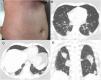

A 43-year-old immunocompetent woman presented to the emergency department with a history of 5 days of high fever (39°C), headache and diarrhea, evolving with a confluent maculopapular rash on her trunk (Fig. 1A). The patient was a resident of São Paulo, Brazil, in which an outbreak of measles was occurring. She had no history of measles vaccination. The diagnosis of measles was confirmed by serological positivity for serum measles immunoglobulin M (IgM) antibodies. No Koplik's spots were observed. One week after the onset of clinical symptoms, the patient began to present respiratory symptoms, with dry cough, dyspnea, chest pain and sore throat. Laboratory tests showed leukopenia with lymphocytosis. Blood cultures were negative. Chest computed tomography (CT) demonstrated multiple peripheral consolidations, mainly in the lower lobes (Fig. 1B–D). Pulmonary embolism was excluded. Bronchoscopy was performed, and microscopic examination of the bronchoalveolar lavage fluid and cultures showed negativity for bacteria and fungi. The patient was managed solely with supportive therapy. Her condition and respiratory distress improved, and she was discharged 7 days after admission.

Most measles-related deaths are caused by complications. The respiratory tract is a frequent site of complication, with pneumonia accounting for most measles-associated morbidity and mortality. Pneumonia can be caused by the measles virus, or by secondary viral or bacterial pathogens.3 These conditions can be difficult to differentiate based on imaging features, as the imaging findings of measles pneumonia are nonspecific. The most common CT findings are ground-glass opacities and consolidations with lobular or segmental distribution, nodules, interlobular septal thickening and bronchial or bronchiolar wall thickening. Other CT findings are bronchiolitis, hyperinsufflation, mosaic attenuation, pleural effusion and lymphadenopathy.1,4 Vaccinated individuals infected with measles can develop nodular pneumonia. These cases can be misdiagnosed due to the absence of specific IgM and typical symptoms.7 Vaccination is the best way to prevent measles, but the live-attenuated virus vaccine is contraindicated in immunocompromised patients.2,6 The management of patients with measles consists of supportive therapy to correct or prevent dehydration and, in some cases, to treat nutritional deficiencies, as well as early detection and treatment of secondary bacterial infections, such as pneumonia and otitis media. High doses of vitamin A have been shown to decrease mortality and the risk of complications. No specific antiviral therapy for measles exists, although ribavirin, interferon alfa, and other antiviral drugs have been used to treat severe cases.2,6